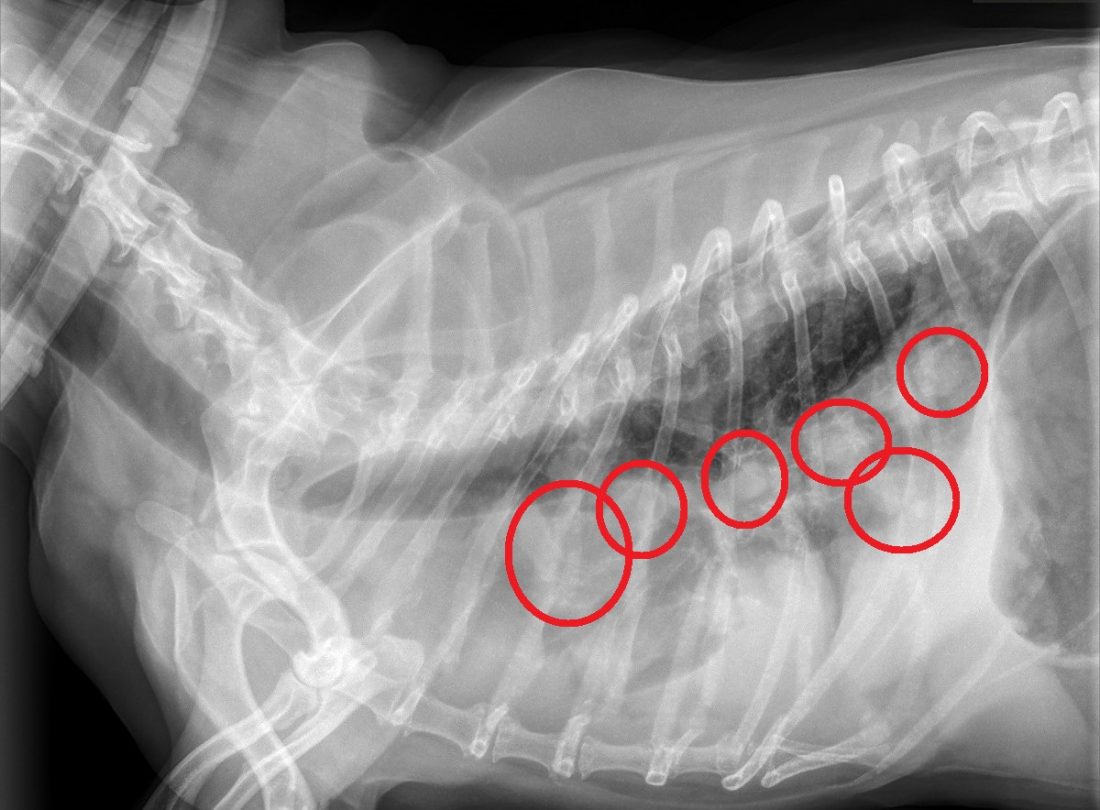

Xray Radiograph of a Dog with Lung Cancer Stock Photo Image of care Dog Chest Tumor If a dog develops these, what other signs might you expect to accompany it? Thoracic wall tumors in dogs refer to abnormal growths that occur in the chest wall, which includes the ribs, muscles, and. While lung tumors are relatively rare in our furry friends, they can creep into a dog’s life and seriously impact their health. If you feel. Dog Chest Tumor.

Chest Xrays in Dogs What's Abnormal? Dog Discoveries Dog Chest Tumor What causes lung cancer in dogs? So what is lung cancer and how do dogs fall victim to this disease? What are some common types of tumors in a dog? Diagnosing lung cancer in dogs. Thoracic wall tumors in dogs refer to abnormal growths that occur in the chest wall, which includes the ribs, muscles, and. We’ll discuss this as. Dog Chest Tumor.

The Enemy Within. A Dog's Battle with Cancer Revealed in Xrays Dog Dog Chest Tumor If a dog develops these, what other signs might you expect to accompany it? Lung cancer is a serious diagnosis in our canine companions. What are some common types of tumors in a dog? If you feel a lump on your dog's chest, it's normal to worry about it. Diagnosing lung cancer in dogs. What are the signs of lung. Dog Chest Tumor.